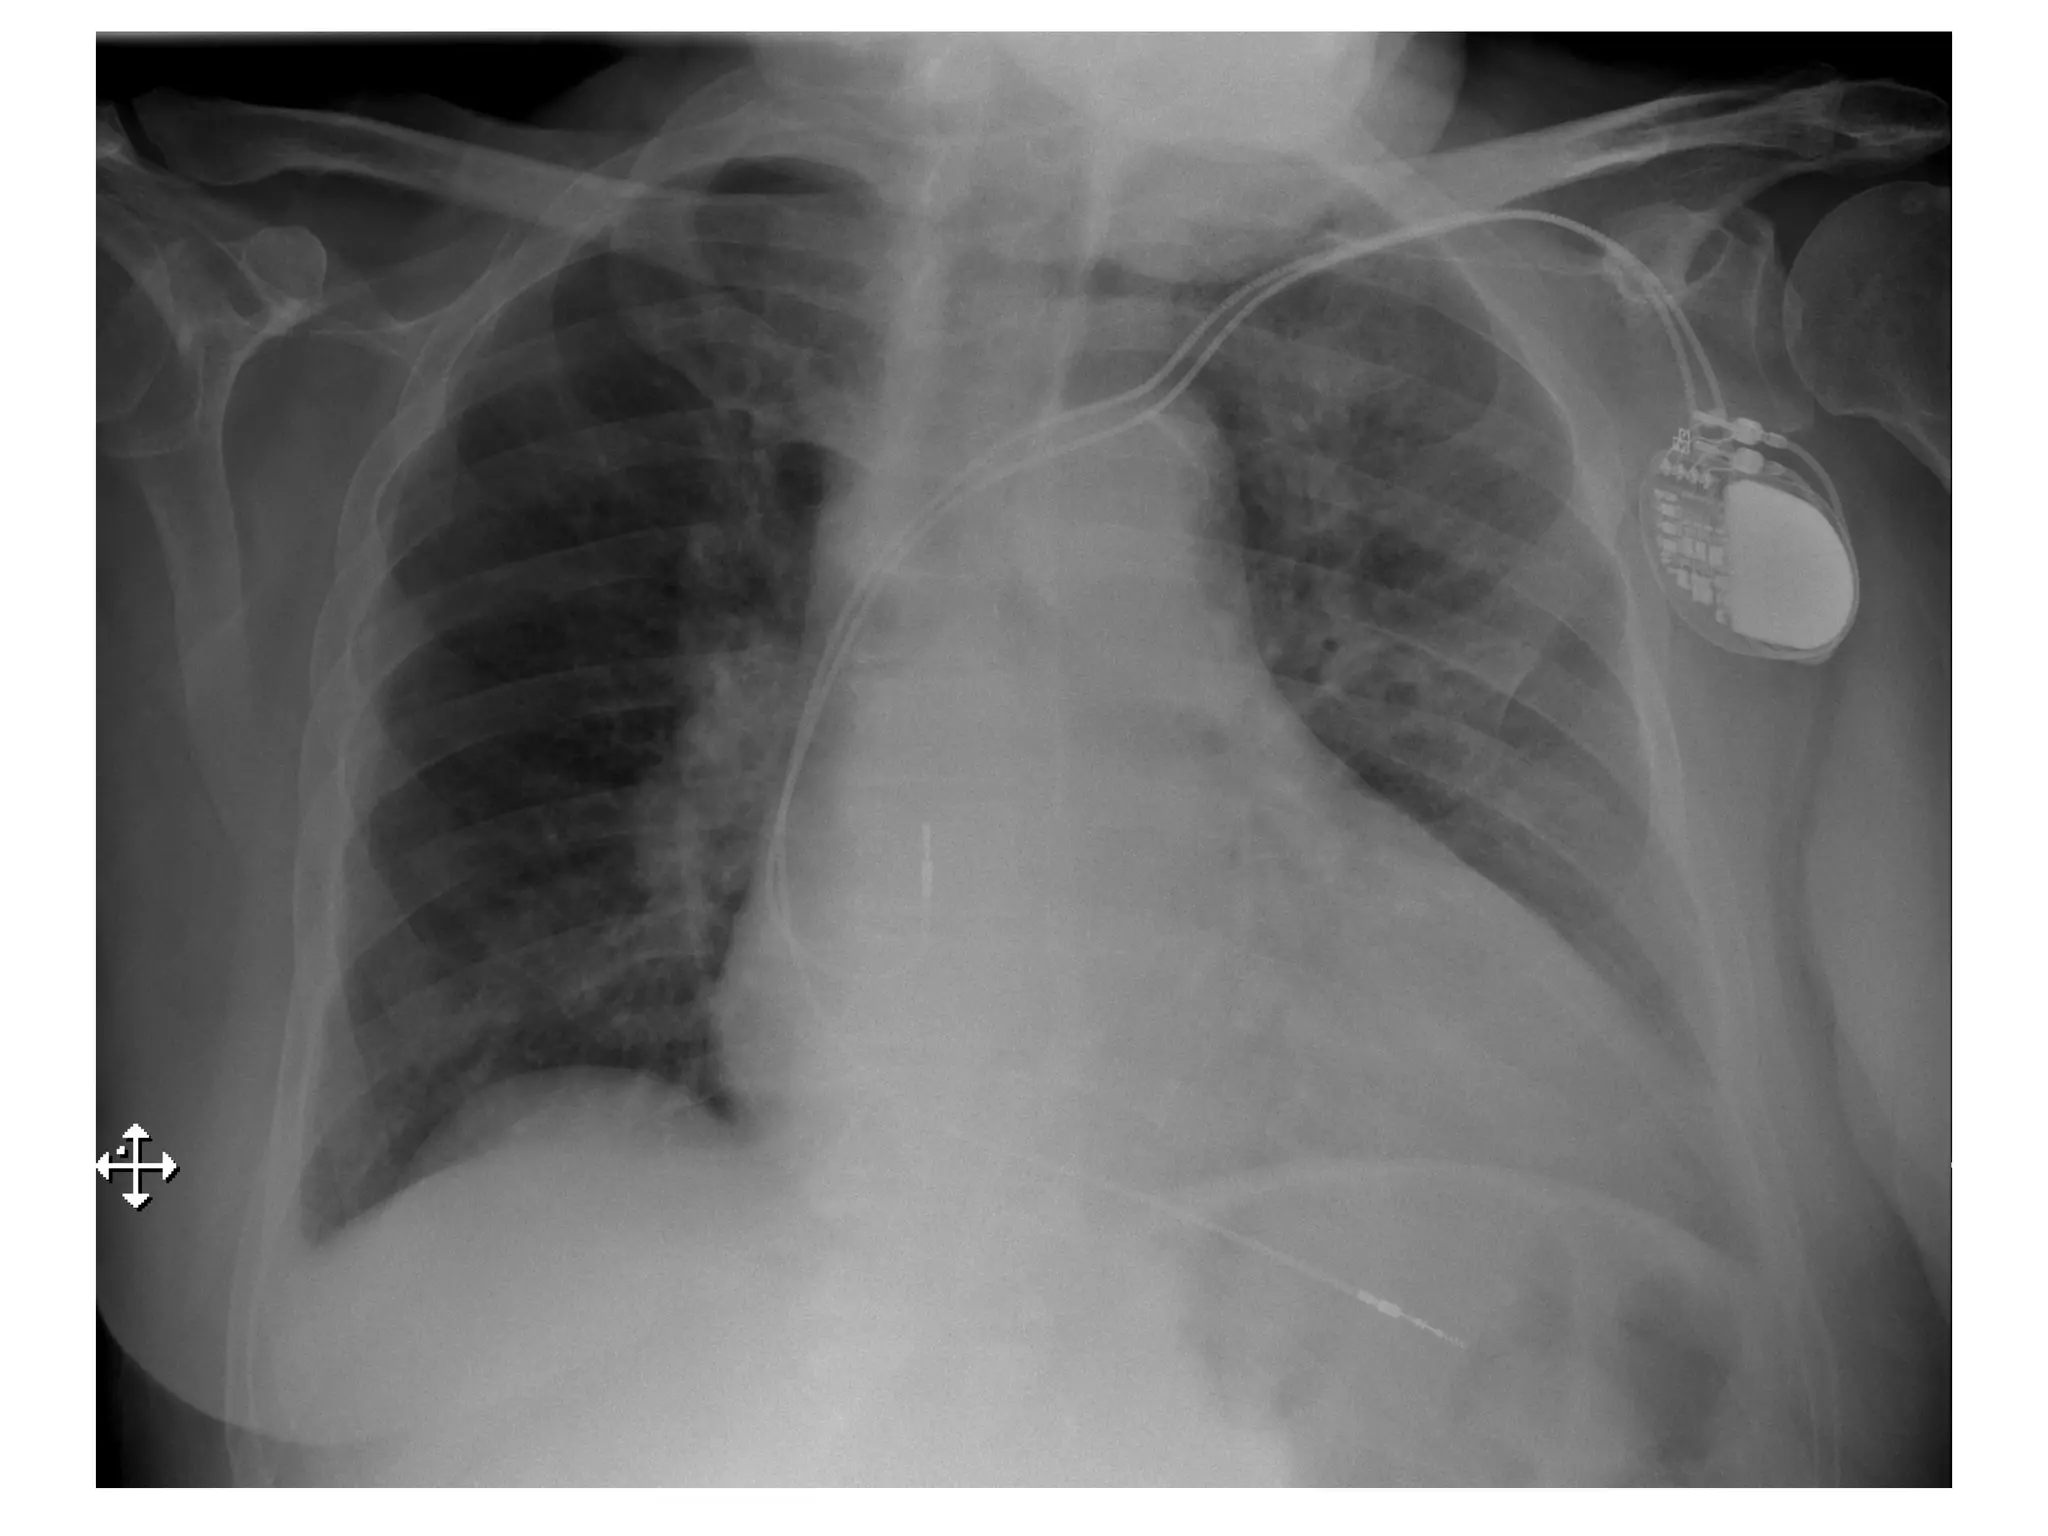

Pacemakers—Today

• Pectoral implants

• 6-7 F transvenous lead

placement

– Outpatient/overnight stay

• < 30 cc

• 8-10 years longevity

• Dual chamber, multi-

programmable

• Advanced diagnostics and